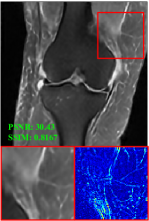

Figure 5 provides the qualitative comparison of the various methods on the four datasets at a scale of 4. The top, second, third, and bottom rows are the SR results under the FastMRI, clinical brain, clinical tumor and clinical pelvic datasets, respectively. The red boxes indicate the zoom-in region of complicated anatomical structures along with their corresponding error maps. Note that the brighter textures in the error maps, the lower the quality of the reconstructed images. As can be seen, compared to methods based on Transformers and CNNs, diffusion-based methods like DisC-Diff and DiffMSR (Ours) are capable of reconstructing high-realistic images with promising reconstruction metric scores (PSNR and SSIM). Nevertheless, while DisC-Diff can reconstruct high-precision MR images, it does not preserve the structure present in the original HR images, introducing some additional information that can affect medical diagnosis. In contrast, our method combines DM and PLWformer, which can preserve the original image’s structure while restoring high-frequency information.

In this section, we present more visual qualitative comparisons. Figures 8, 9, 10, and 11 show the reconstruction results of each method in FastMRI, clinical brain, clinical tumor, and clinical pelvic, respectively. As can be seen, although DisC-Diff can reconstruct MR images with high-frequency information, it fails to preserve the structure and content of the original Target HR image effectively, resulting in image distortion. In contrast, our proposed DiffMSR can restore high-frequency information while preserving the structure of the original HR image, indicating the effectiveness of the joint use of DM and PLWformer.

Besides, our proposed method can be modified to the Single-Contrast Super-Resolution (SCSR) method by removing the cross-attention Transformer layer. The visual qualitative results are shown in Figure 12. As can be seen, our method outperforms other DM-based SCSR methods in the SCSR task.